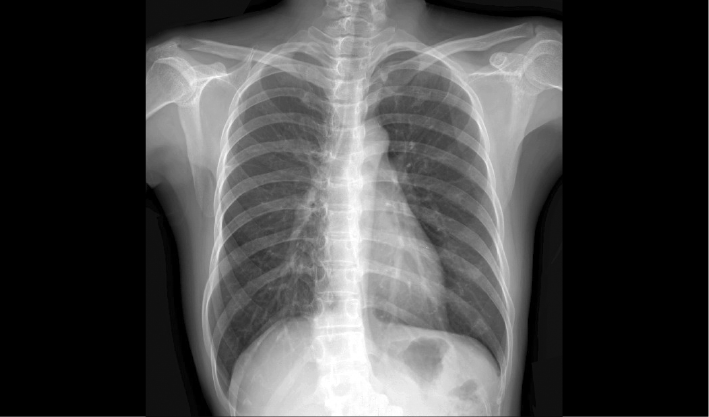

配合十軸智能全自動操控,實現六向跟蹤和一鍵自動擺位切換,融合高端配置,帶來一流的圖像,簡便操控,快捷流程,輔助醫生快速精準診斷。

消除線噪聲的同時不損失圖像細節,保持邊緣和分辨率,不會引入新偽影,增加圖像銳利度。